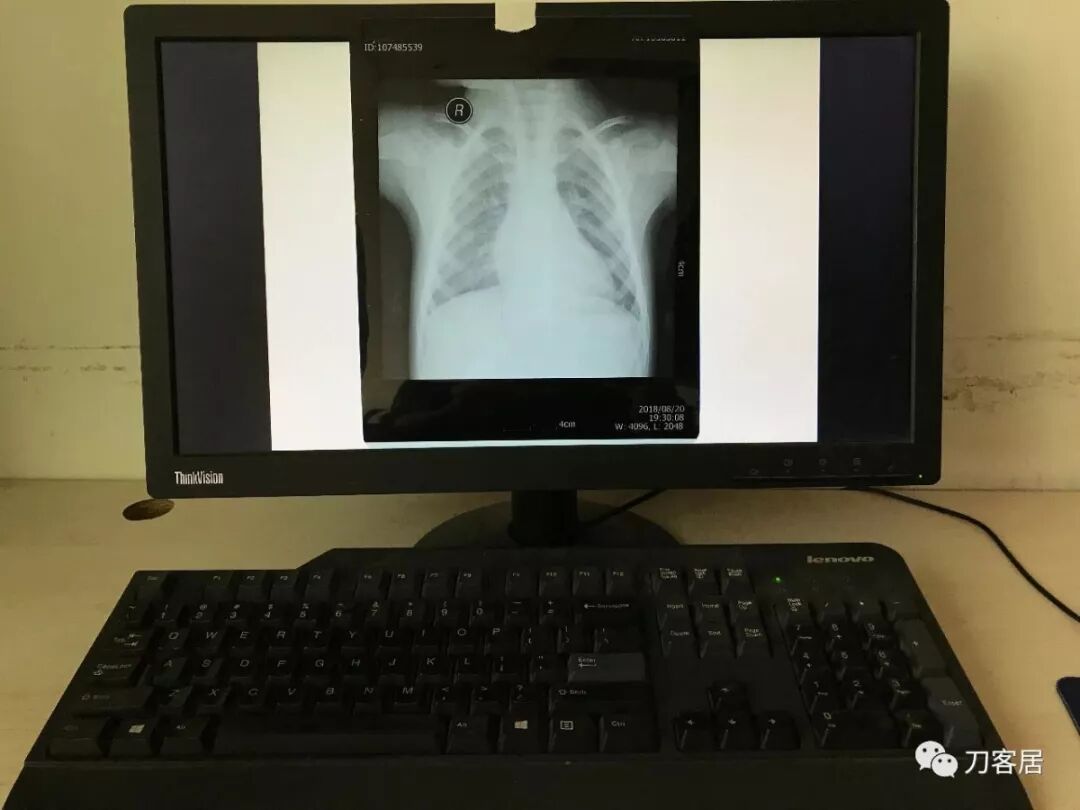

如果家里有电脑(台式机或笔记本电脑均可),也可以使用电脑显示器调白色后进行拍摄。

使用电脑拍摄的时候,在电脑打开幻灯软件Powerpoint (PPT),新建一个空白文档,纯白色的,然后把该文档全屏播放模式下,即可实现全屏白色(图7,图8)。

图7

图8